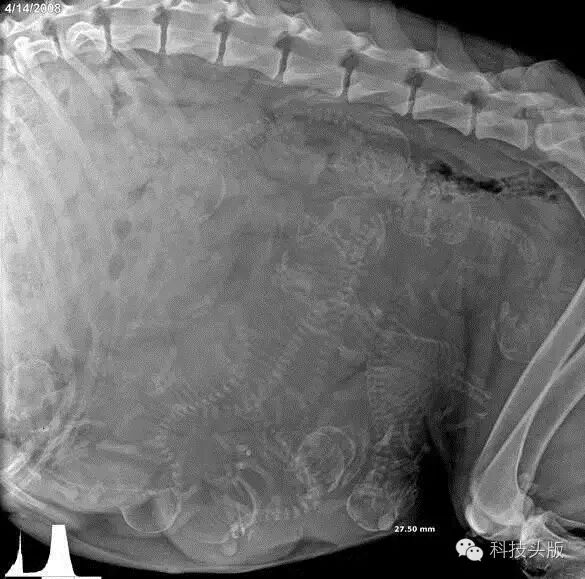

这是一只怀孕的狗狗,鼓囊囊的满肚子里都是小生命。